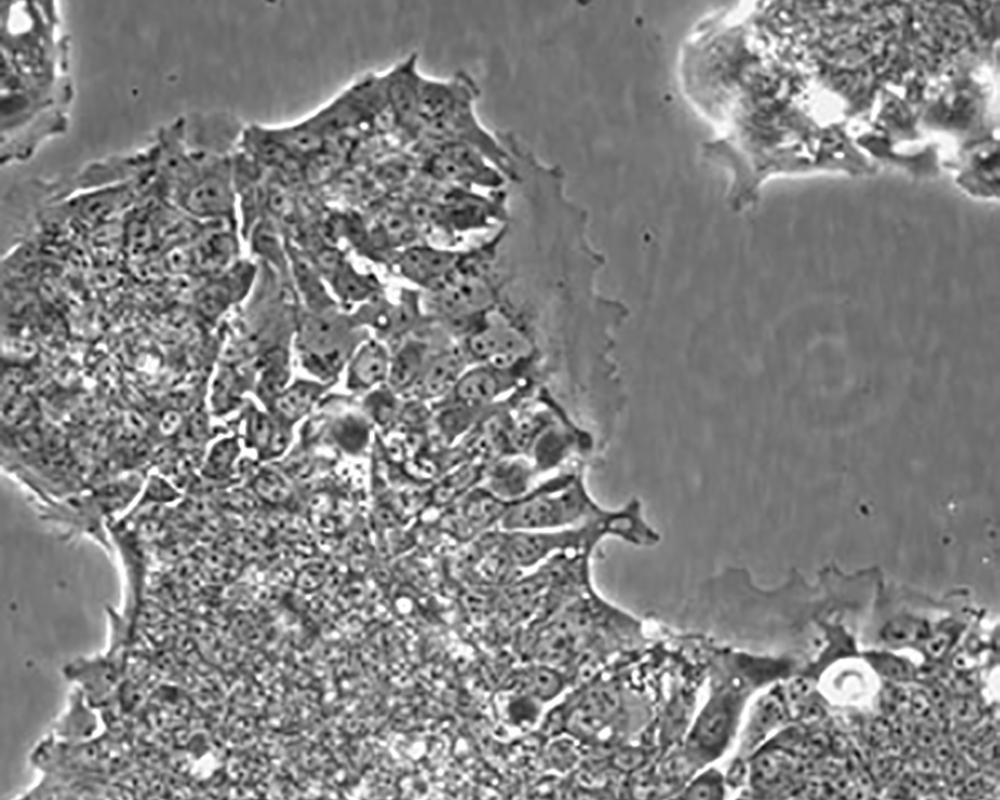

形態(tài)特征 epithelial

細胞描述 T84細胞株是從一位72歲男性結腸癌患者的肺轉(zhuǎn)移灶建立的可移植人類癌細胞株。 腫瘤組織皮下接種于BALB/c裸鼠,并連續(xù)進行移植。 [26072] 在裸鼠身上的移植過程中,細胞株始終保持結腸癌的原始組織性狀。 [26072] 在無胸腺小鼠中傳代23代后建立了T84細胞株。 這些細胞單層生長到飽和并在接觸細胞間展現(xiàn)出緊密連接和橋粒。 [1155] 有很多關于多肽類激素和神經(jīng)遞質(zhì)并維持定向電解質(zhì)傳輸?shù)氖荏w。 [1155] 這株細胞展現(xiàn)了接觸細胞中的緊密連接和橋粒。 [1155] 角蛋白免疫過氧化物酶染色陽性。